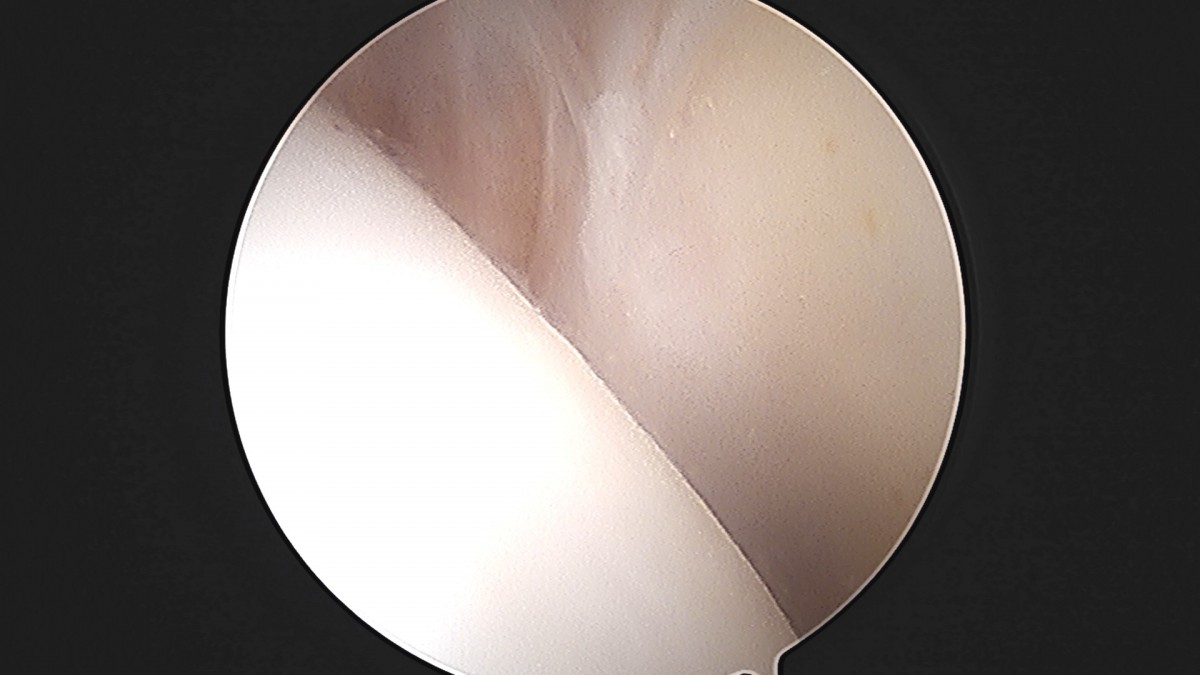

정지영원장님 발목 인대 봉합술 채이O 환자

작성자 최고관리자 댓글 0건 조회 718회 작성일 25-09-16 17:02